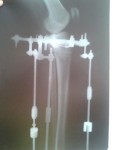

2 месяца с момента операции.

Регенерат растёт хорошо, продолжаем сращение.

Спасибо за совет, Василек! Как на фото ноги мои, ровные со стороны виднее все таки, что- то как -то не пойму какие они получились?!

Привет Adina! Ножки у тебя хорошенькие... Немного иксик есть, но уж лучше так, чем недокрученные. А так они ещё меняться будут с течением времени, так что полностью картинкой ты сможешь насладиться только через несколько месяцев после снятия аппаратов. Как то так...